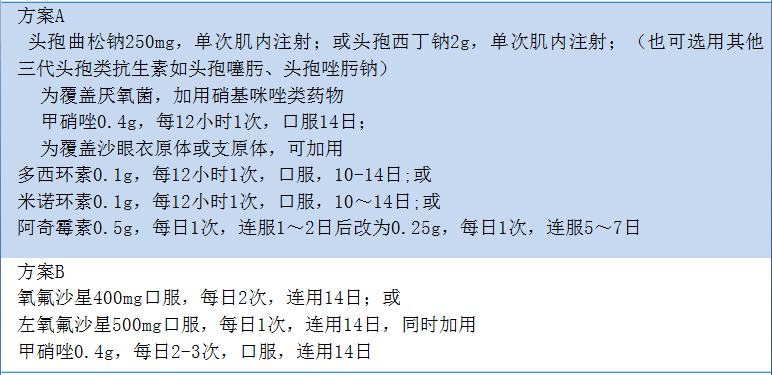

1.门诊治疗 若患者一般状况好,症状轻,能耐受口服抗生素,并有随访条件,可在门诊给予非静脉应用(口服或肌内注射)抗生素,常用给药方案见表20-2。

表20-2 PID非静脉给药方案